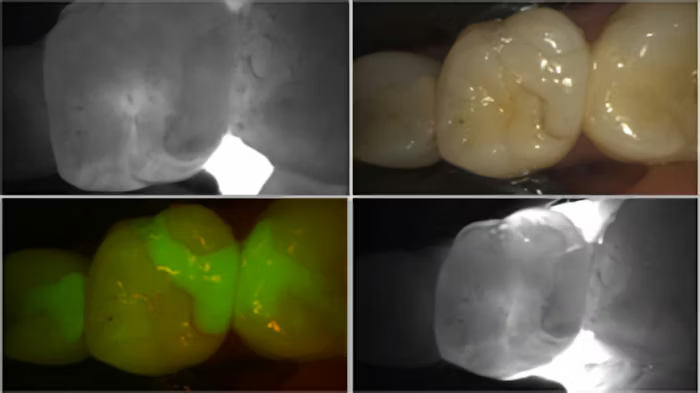

Enamel possesses a certain translucency, allowing light to pass through without interruption. A cavity, on the other hand, creates an opacity (a shadow). Therefore, when illumination is applied buccolingually, the cavity is easy to identify. This is valuable for both the identification of dental caries but also for determining the extent of the decay.

The transillumination mode, however, for me, was the game changer. The DIAGNOCam’s special tip emits near-infrared light at the gingival level, from both the buccal and lingual aspects. The near-infrared light transmits through healthy enamel toward the camera, which has a corresponding bright, white appearance on the resulting image. Areas of carious or demineralized enamel scatter the light, resulting in a corresponding darker region.

Using the same radiograph from above [Figure 4], I transilluminated the questionable areas, yielding highly accurate discernment of the extent and location of various cavities.